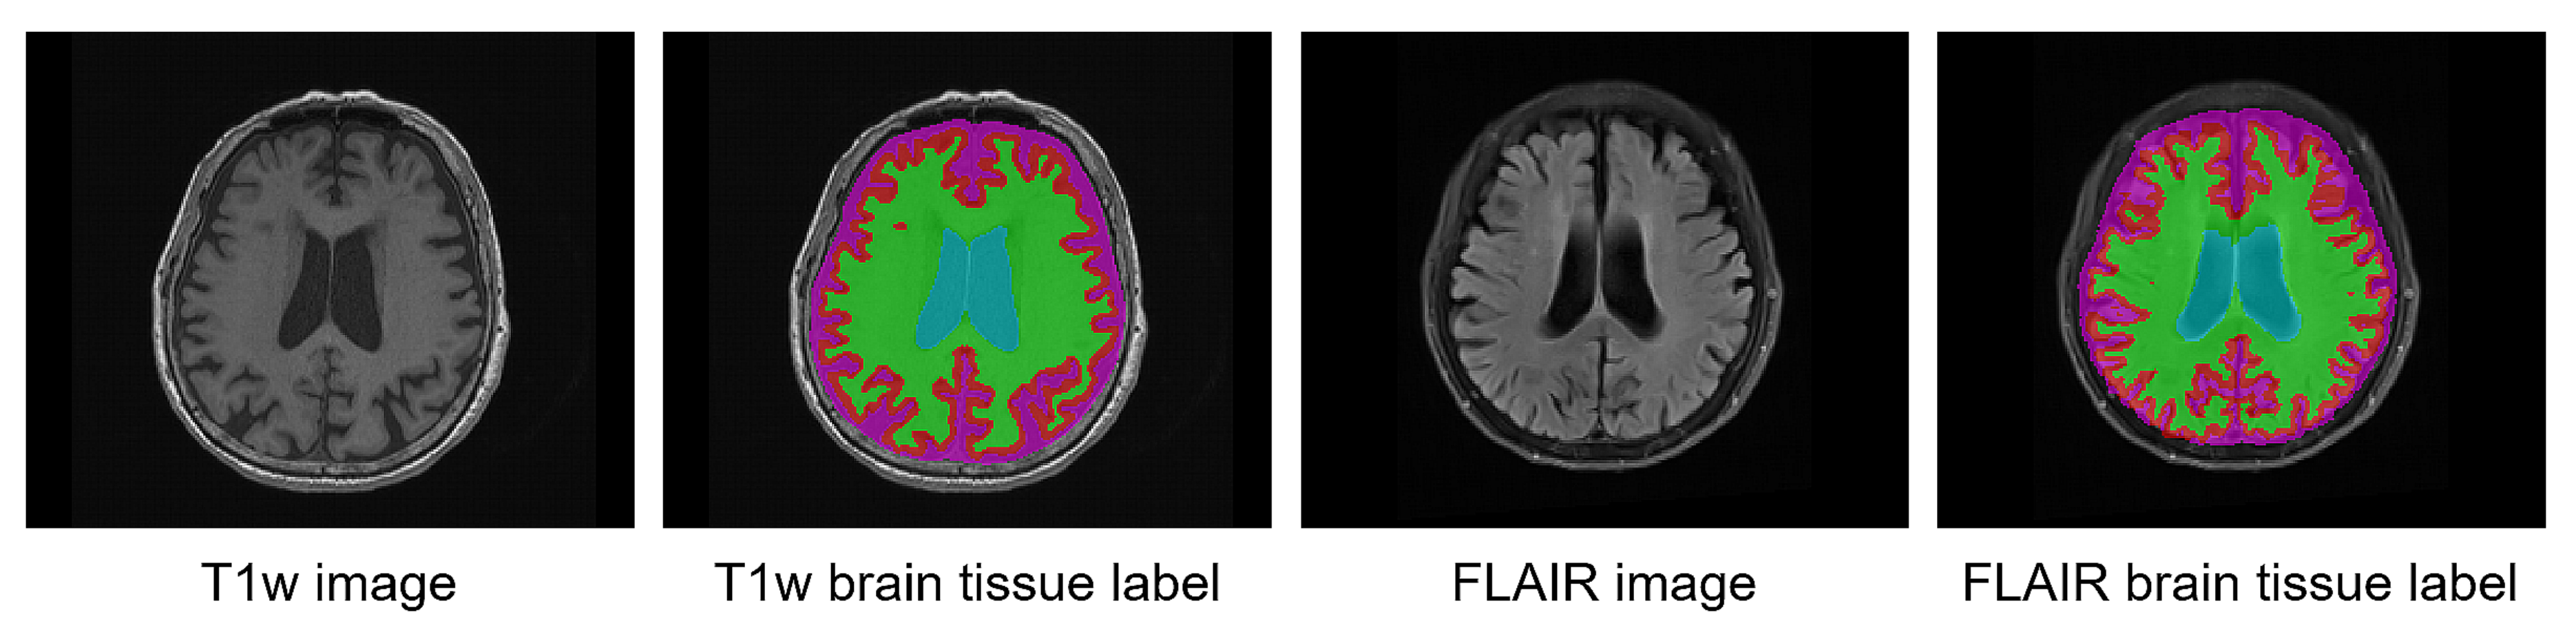

2.3.1. Pseudo-Labeling from T1w MRI

2.3.2. Co-Registration